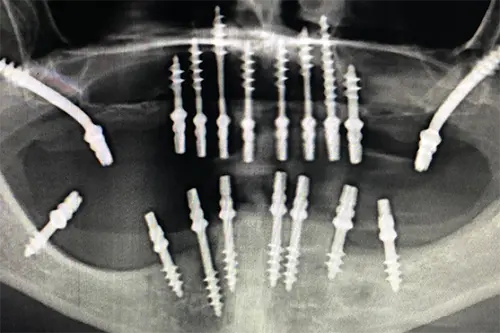

Basal Implants (IHDE Implants System)

Immediate loading implants, perfect for complex cases with minimal bone density.